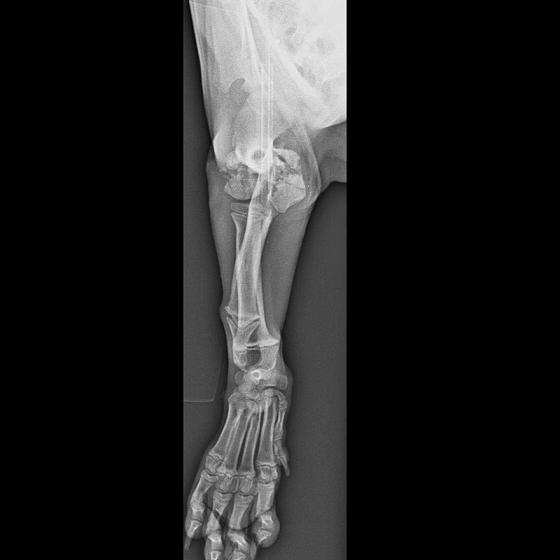

Pluto dnes absolvoval druhú operáciu. Vyberala sa platnička a veľká skrutka, ktorá sa nahradila menším pinom. Koncom mesiaca ho čaká ďalšia a dúfame, že už posledná operácia. Také malinké šteniatko a už toľko bolesti musí prežívať :( Má sa dobre, rastie do krásy a už sa pomaly može naplno šantiť so svojim kamošom v dočasnej opatere. :) Veľmi pekne prosíme, pomôžte nám s úhradou faktúr. Faktúry nájdete priebežne v galérii a na konci článku aj zoznam darcov s prijatou aj chýbajúcou sumou. Po poslednej operácii čakajú Pluta ešte mesiace rehabilitácie, aby sa nožička úplne rozhýbala a mohol ju používať naplno :)

Odoberal sa od drogovo závislých asociálov, ktorý boli vysťahovaný z domu. Ihly, striekačky, ľudské výkaly, rôzne neidentifikovateľné zvratky, špinavé oblečenie, použité kondómy - to všetko nahádzané na jednu kopu v obývačke, kde Pluto so svojou maminkou Miou žili. :( Nevieme ako sa to stalo, kto mu ublížil, ale Pluto má prestrelenú prednú nohu! Viete si predstaviť toho psychicky narušeného človeka, ktorý strieľa na malé bezbranné šteniatko? V dôsledku strelnej rany má doslova rozdrvenú lakťovú kosť. Mali sme veľké obavy, že o nožičku príde, ale MVDr. Vatolík s teamom veterinárnej kliniky Sibra centrum opäť urobil zázrak a malému nožičku napravil a prognóza je viac než dobrá. Čaká ho ešte dlhá cesta k zotaveniu, ale je to odvážny a statočný bojovník. Nechceme si ani len predstaviť čím všetkým si tie zvieratká muesli prejsť, a kto vie koľko ich pôvodne bolo.. Nikto nevie ako a kde skončili Plutovi súrodenci...